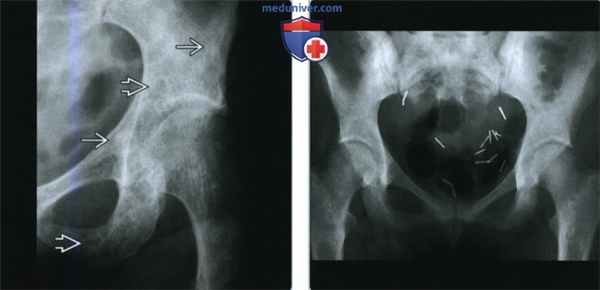

(Слева) Рентгенография в ПЗ проекции: многочисленные округлые патологические очаги, диаметром около сантиметра. Характер очагов различный: полностью склеротический или литический со склеротическими краями. Очаги со склеротическим краем являются вариантом полностью склеротических очагов, встречающихся при POEMS.

(Справа) Рентгенография в ПЗ проекции: диффузный склероз таза и нечеткие округлые очаги в шейках бедренных костей. Это вариант склеротических костных очагов при POEMS, при котором склероз характеризуется в большей степени диффузный, а не очаговый.

2. Рентгенография при POEMS:

• Костные очаги:

о Солитарное поражение 42%, 2-3 очага - 29%, >3 очагов - 29%

о В 47% случаев-только склеротические очаги; в 51% - смешанные литические и склеротические очаги:

- Округлые, полностью склеротические очаги

- Округлые литические очаги со склеротическим краем

- Диффузный склероз в области поражения; отсутствие фокальных очагов